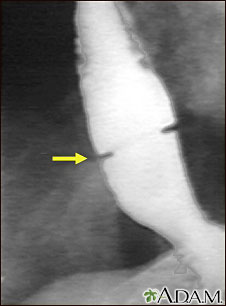

A solution containing a dye (barium), which is visible on X-rays, has been swallowed (upper GI series) and X-rays have been taken of the esophagus. There is a narrowing near the stomach (indicated by the arrow). This non-cancerous ring of tissue (Shatzki's ring) may cause swallowing problems (dysphagia) and can be treated with dilation of the stricture.